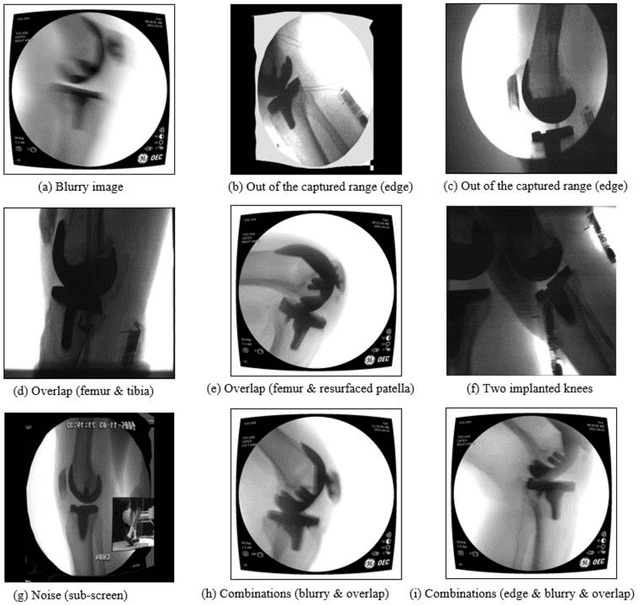

Abstract:Image segmentation in total knee arthroplasty is crucial for precise preoperative planning and accurate implant positioning, leading to improved surgical outcomes and patient satisfaction. The biggest challenges of image segmentation in total knee arthroplasty include accurately delineating complex anatomical structures, dealing with image artifacts and noise, and developing robust algorithms that can handle anatomical variations and pathologies commonly encountered in patients. The potential of using machine learning for image segmentation in total knee arthroplasty lies in its ability to improve segmentation accuracy, automate the process, and provide real-time assistance to surgeons, leading to enhanced surgical planning, implant placement, and patient outcomes. This paper proposes a methodology to use deep learning for robust and real-time total knee arthroplasty image segmentation. The deep learning model, trained on a large dataset, demonstrates outstanding performance in accurately segmenting both the implanted femur and tibia, achieving an impressive mean-Average-Precision (mAP) of 88.83 when compared to the ground truth while also achieving a real-time segmented speed of 20 frames per second (fps). We have introduced a novel methodology for segmenting implanted knee fluoroscopic or x-ray images that showcases remarkable levels of accuracy and speed, paving the way for various potential extended applications.